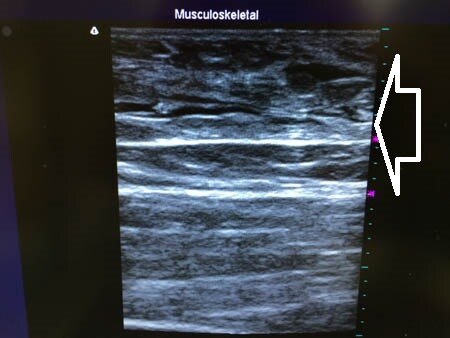

上の画像の部分をつまんでみましょう。

同様に右太もも正面。